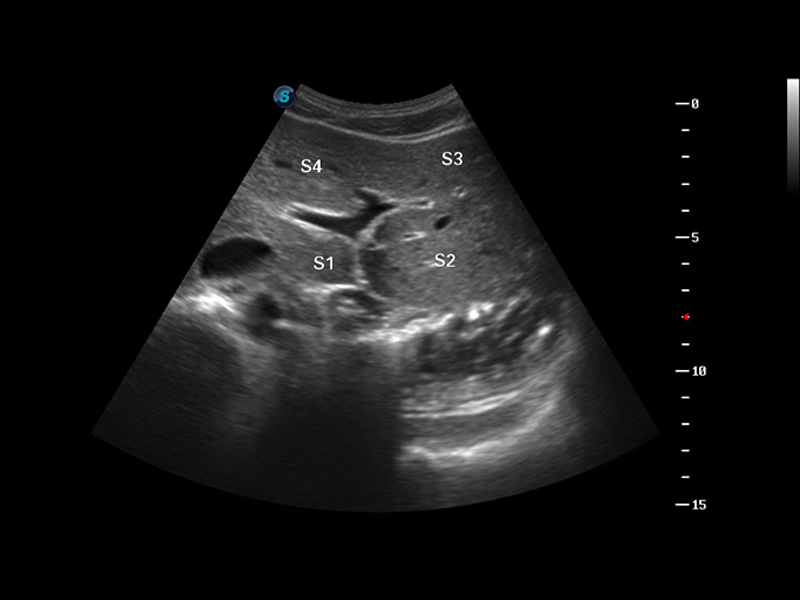

S8 EXP便携式彩色多普勒超声诊断仪是狗万官方网站研发的高端全身应用型便携彩超。高通道的VIS平台融合可视化(Visual)、智能化(Intelligent)和人性化(Smart)的特点,配以狗万官方网站自主研发生产的探头大家族,使您能够快速、准确的获得病人信息,提高工作效率的同时减轻疲劳。

成像技术

μ-Scan微米成像

谐波成像

实时宽景成像

空间复合成像

3D/4D成像